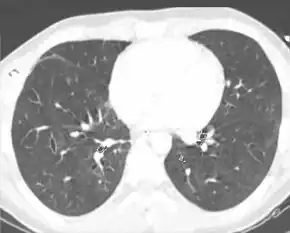

| A CT scan showing a pulmonary contusion (red arrow) accompanied by a rib fracture (blue arrow) | |

Computed tomography (CT scanning) is a more sensitive test for pulmonary contusion,[3][32] and it can identify abdominal, chest, or other injuries that accompany the contusion.[37] In one study, chest X-ray detected pulmonary contusions in 16.3% of people with serious blunt trauma, while CT detected them in 31.2% of the same people.[45] Unlike X-ray, CT scanning can detect the contusion almost immediately after the injury.[42] However, in both X-ray and CT a contusion may become more visible over the first 24–48 hours after trauma as bleeding and edema into lung tissues progress.[46] CT scanning also helps determine the size of a contusion, which is useful in determining whether a patient needs mechanical ventilation; a larger volume of contused lung on CT scan is associated with an increased likelihood that ventilation will be needed.[42] CT scans also help differentiate between contusion and pulmonary hematoma, which may be difficult to tell apart otherwise.[47] However, pulmonary contusions that are visible on CT but not chest X-ray are usually not severe enough to affect outcome or treatment.[36]